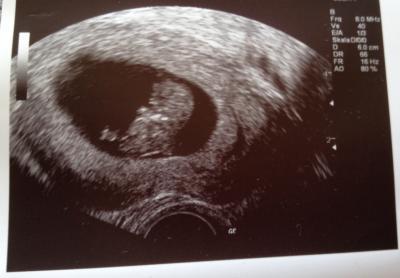

Heute stand ein außerplanmäßiger FA-Besuch auf dem Plan, da ich mich gestern ordentlich mit dem Fahrrad auf die Nase gelegt habe. Dem Krümel geht's super & die blauen Flecken, sowie Prellungen werden hoffentlich wieder schnell vergessen sein. Etwas positives hatte der Besuch, ich konnte unser Würmchen auf dem Ultraschall sehen und ich muss sagen: Ich bin verliebt! So süß, wie es sich bewegt hat und das kleine Herzchen gepocht hat!

Bild zu außerplanmäßiger FA-Besuch - Forum für Mai - Mamis